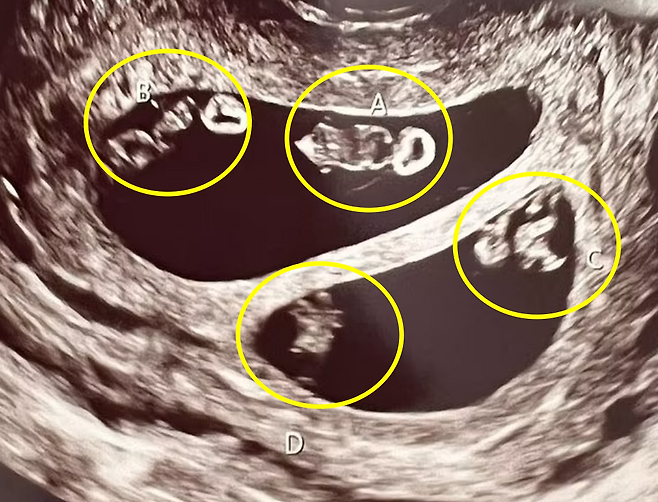

임신이라는 사실을 직감한 뒤 병원을 찾았을 때, 초음파 검사를 하던 담당 의사는 의아함에 고개를 갸우뚱거렸다. 그녀의 자궁 안에서 총 4명의 태아가 자라고 있으며, 이는 네 쌍둥이가 아닌 일란성 쌍둥이 2쌍으로 추정됐기 때문이다.

네스의 자궁에서 자라는 일란성 쌍둥이는 남자아이 2명, 여자아이 2명으로 확인됐다.

담당 의사는 “네 쌍둥이가 아닌 일란성 쌍둥이 두 쌍을 동시에 임신하는 경우는 처음 봤다. 당초 초음파 검사를 통해 이를 확인했을 때, 이런 ‘현상’이 가능한 지 알수가 없어서 곧바로 관련 자료를 찾아봐야했다”고 전했다.

ABC뉴스는 “두 개의 각기 다른 난자가 수정되고, 각각의 수정란이 또다시 분리되면 일란성 쌍둥이 두 쌍을 동시에 임신하는 것이 가능하다”고 설명했다.